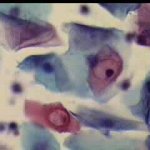

Ιατρικές Εικόνές - Κοιλοκυττάρωσης και υπερκεράτωσης.

Για τις ανάγκες επίδειξης περιστατικών στο forum του www.gyn.gr , θέτουμε στην διάθεση των επισκεπτών χαρακτηριστικές κυτταρολογικές εικόνες, που αφορούν το εύρημα της κοιλοκυττάρωσης στο επίχρισμα κατά Papanicolaou. Το υλικό προέρχεται από περιστατικά του ιατρείου, η χρωση του επιχρισματος δική μας, η απεικόνιση επίσης.